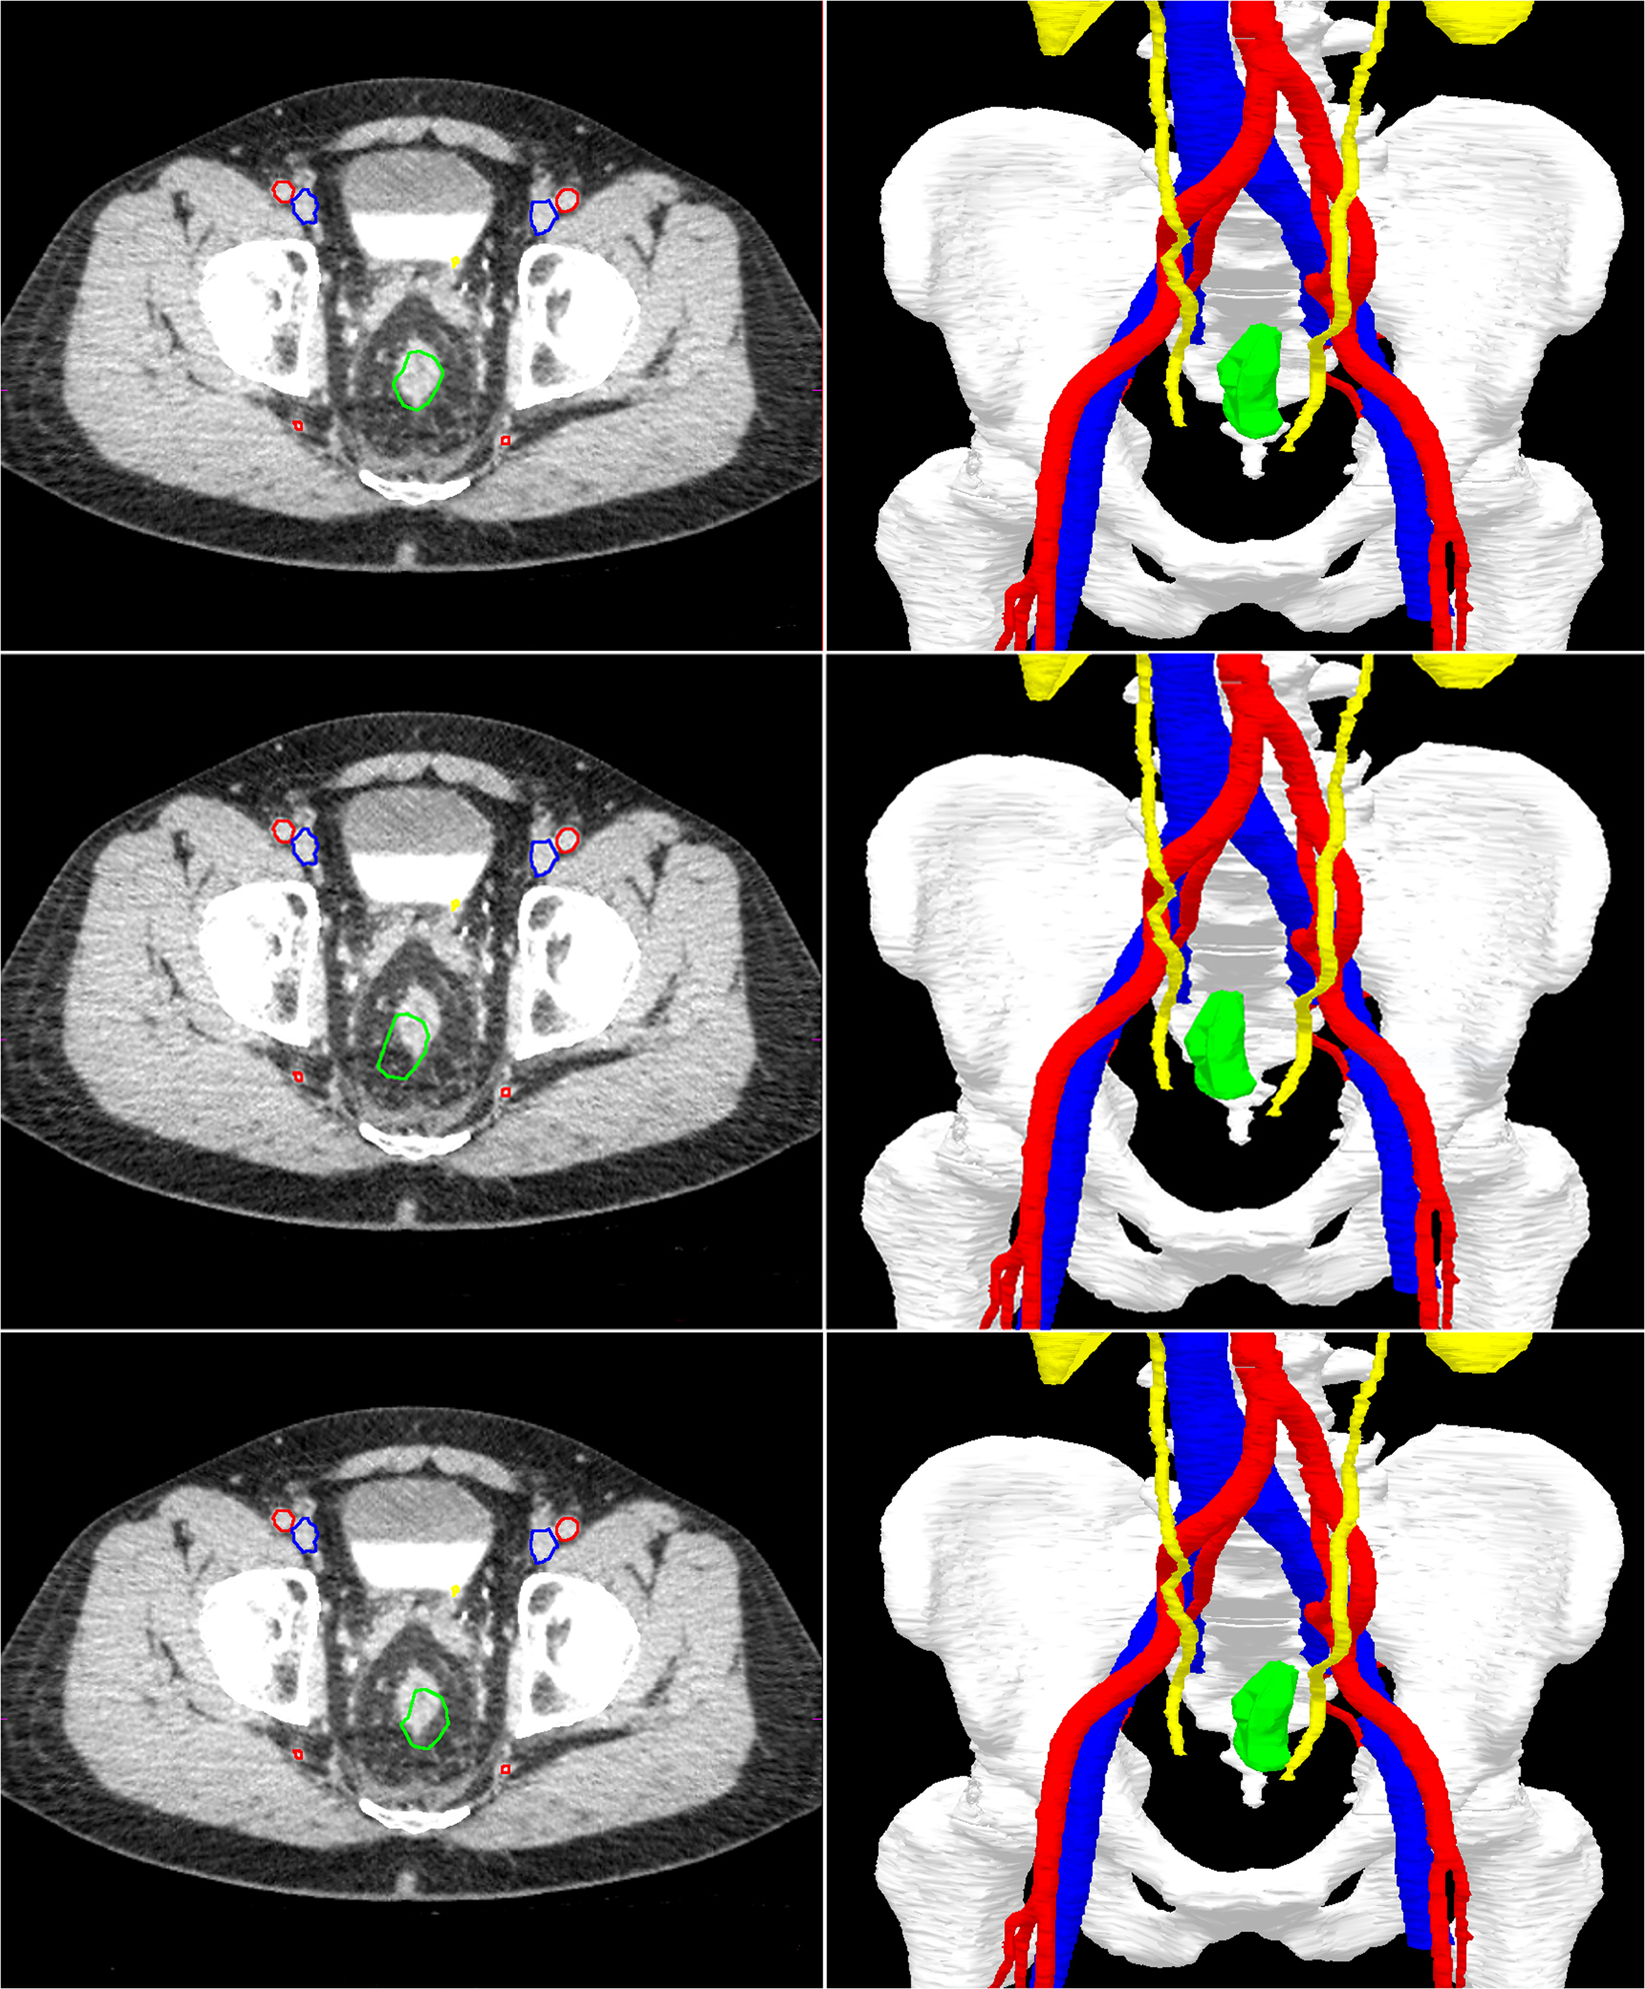

Fig. 3: An example to illustrate the real-time tumor tracking by the navigation system.

The top two images show the position of the rectal tumor in rest. In the lower four images, the rectum is moved to the right and left. Note that the green segmentation area follows the real-time tumor position in the navigation images on the right, while the CT scan on the left (still) shows the original position of the tumor. Visible segmentation: bones (white), arteries (red), veins (blue), ureters/kidneys (yellow), and tumor (green).